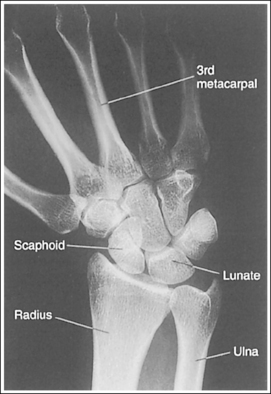

See Figure 4-36 and Box 4-13.

Contrast and density are adequate to demonstrate the pronator fat stripe and surrounding posterior wrist soft tissue.

• The pronator fat stripe is one of the soft tissue structures that should be demonstrated on all lateral wrist projections (Figure 4-37). It is located parallel to the anterior (volar) surface of the distal radius, is normally convex, and lies within 0.25 inch (0.6 cm) of the radial cortex. Bowing or obliteration of this fat stripe may be the only indication of a subtle radial fracture.

The wrist is in a lateral projection. The anterior aspect of the distal scaphoid and pisiform are aligned, and the radius and ulna are superimposed.

• A lateral projection of the wrist is accomplished by flexing the elbow 90 degrees and abducting the humerus until it is parallel with the IR, placing the entire arm on the same horizontal plane. Rotate the wrist into a lateral projection with its ulnar (medial) aspect against the IR (Figure 4-38). To ensure a true lateral projection, place the palmar aspect of your thumb and forefinger against the anterior and posterior aspects, respectively, of the patient's wrist joint, as shown in Figure 4-39. Adjust wrist rotation until your thumb and finger are aligned perpendicular to the IR.

• Detecting wrist rotation. The relationship between the pisiform and distal aspect of the scaphoid can best be used to discern whether a lateral wrist projection has been obtained. On a lateral projection, these two carpals should be superimposed, with their anterior aspects aligned. When the wrist is rotated, the anteroposterior relationship between the distal scaphoid and pisiform changes, and the pronator fat stripe is obscured. If the anterior aspect of the distal scaphoid is positioned posterior to the anterior aspect of the pisiform, the patient's wrist was externally rotated (see Image 45). If the anterior aspect of the distal scaphoid is positioned anterior to the anterior aspect of the pisiform, the patient's wrist was internally rotated (see Images 46 and 47). A second method of determining how to reposition a rotated lateral wrist projection uses the radius and ulna. The ulna is positioned anterior to the radius when the wrist was externally rotated and the ulna is positioned posterior to the radius when the wrist was internally rotated. Because the exact amount of superimposition of the radius and ulna depends on the position of the humerus, and their poor positioning is not as sensitive, you should always view the pisiform and distal scaphoid relationship when determining whether the wrist is in a lateral projection.

The carpal bones do not indicate radial or ulnar deviation. The distal aspect of the distal scaphoid is aligned with the distal aspect of the pisiform.

• To obtain a neutral lateral wrist projection, align the long axes of the third metacarpal and the midforearm parallel with the IR. When the proximal forearm is higher or lower than the distal forearm, the wrist is radial-deviated or ulnar-deviated, respectively. In radial and ulnar deviation the distal scaphoid moves but the pisiform's position remains relatively unchanged. Radial deviation of the wrist forces the distal scaphoid to move anteriorly and proximally (Figure 4-40), causing the distal aspect of the distal scaphoid to be positioned proximal to the distal aspect of the pisiform (see Image 49). Ulnar deviation shifts the distal scaphoid posteriorly and distally (see Figure 4-40), causing the distal aspect of the distal scaphoid to be positioned distal to the distal aspect of the pisiform (see Image 50). The degree of pisiform and distal scaphoid separation is usually very small, because you would be unlikely to position a patient in maximum wrist deviation without being aware of the positioning error. To obtain optimal lateral wrist projections, however, you must learn to eliminate even small degrees of deviation.

The long axis of the first metacarpal is aligned parallel with the forearm.

• If the long axis of the first metacarpal is positioned adjacent to the second metacarpal and aligned parallel with the forearm, the patient's wrist is placed in a neutral position.

• When the wrist is flexed or extended, the positions of the scaphoid and lunate are altered. In wrist flexion the lunate and distal scaphoid tilt anteriorly (see Image 51). In wrist extension the lunate and distal scaphoid tilt posteriorly (see Image 52). Flexion and extension, lateral wrist projections may be specifically requested to demonstrate wrist joint mobility.

The ulnar styloid is demonstrated in profile posteriorly.